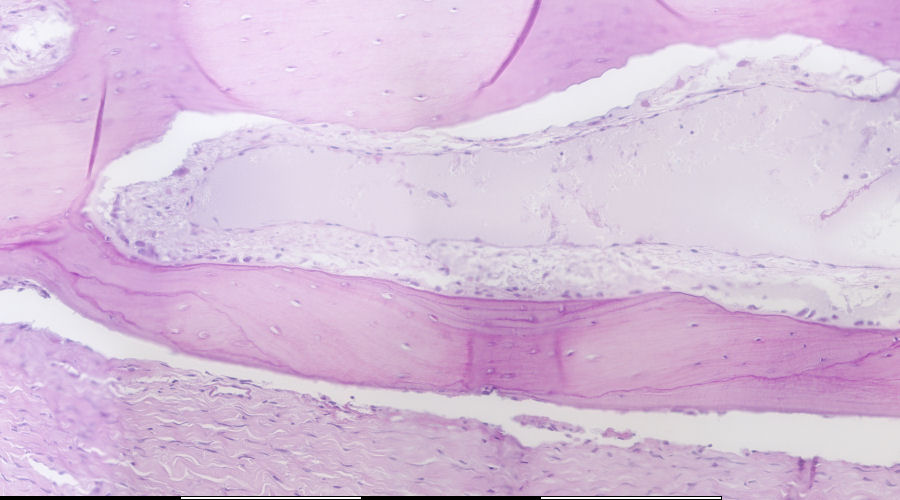

Bone-remodeling unit

Groeilyne / Growth reversal lines Osteoklast / Osteoclast Osteoblaste / Osteoblasts